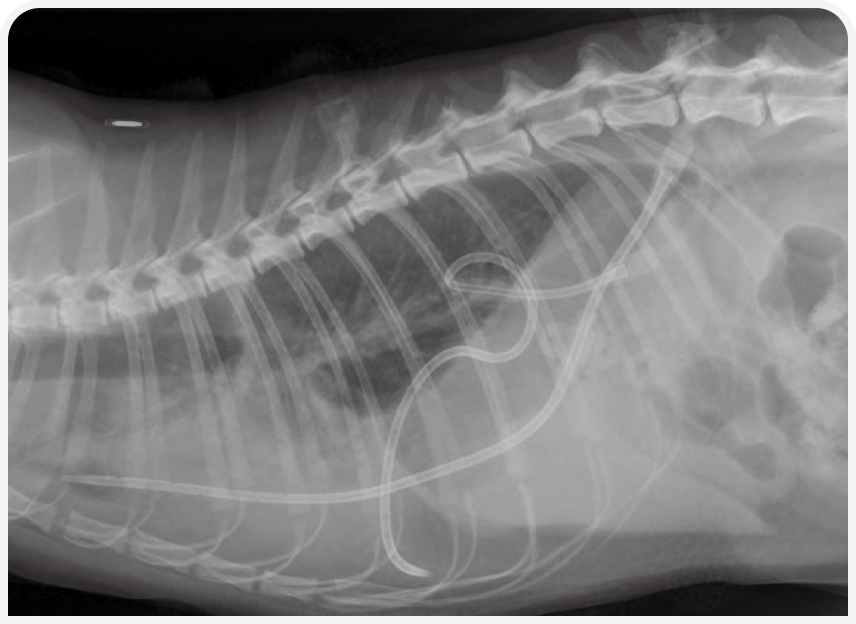

Для оценки степени плеврального выпота, определения одностороннего или двустороннего поражения и выявления любой возможной основной причины, такой как объемные образования в легких или средостении и пневмония, часто проводят рентгенографию органов грудной клетки (4, 6). Рентгенография также позволяет оценить правильность установки торакостомической трубки и эффективность выбранной терапии.

Дренажи, в зависимости от расположения плеврального выпота, следует устанавливать с одной или двух сторон (Рисунок 3). Сразу после введения к дренажной трубке подключают отсос, так как нередко ее размещение вызывает легкий ятрогенный пневмоторакс. После дренирования грудной клетки SBTT прикрепляют к коже; если состояние животного стабильное, то выполняют рентгенографию органов грудной клетки, чтобы оценить положение дренажа.

При рентгенографии может оказаться, что катетер находится в плевральной полости не в предполагаемом положении, но, если он функционирует и других нарушений не отмечено, заменять его не следует (Рисунок 4).